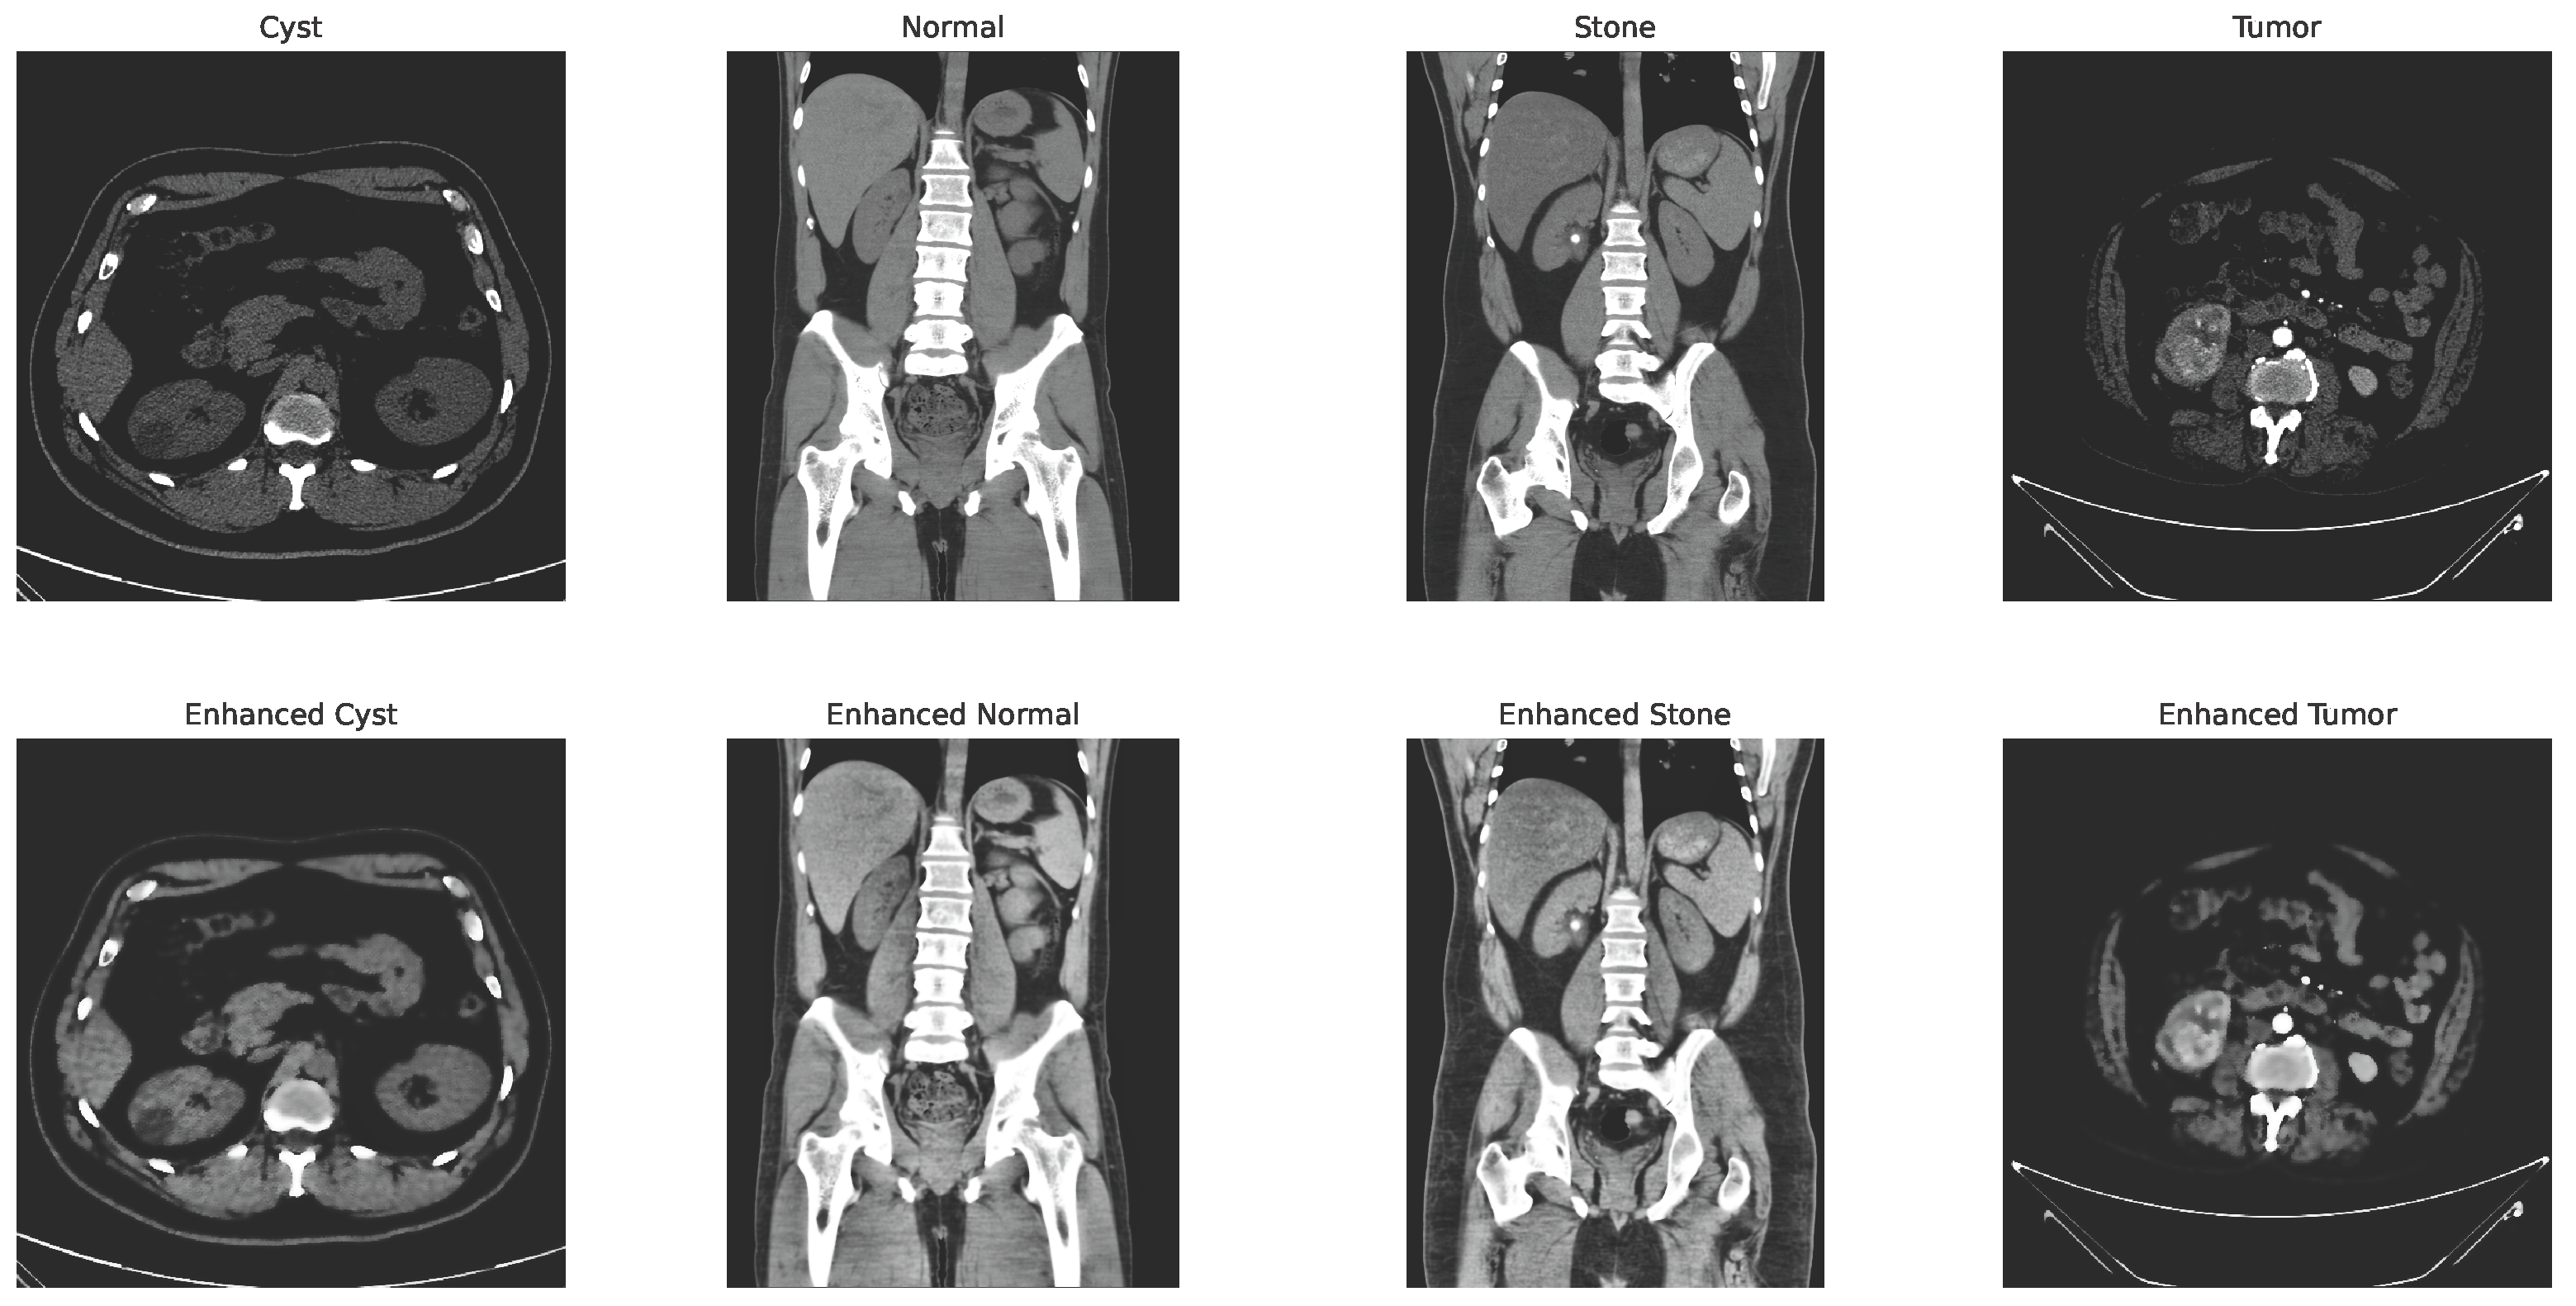

Some of the examples of the ct images of four classes are shown in Figure 3.

Figure 3.

Examples of cyst, normal, stone, and tumor CT image.

with and representing the spatial and range kernel functions, denoting the neighborhood, and acting as a normalization factor. Figure 4 shows the changes in the image after applying the CLAHE and bilateral filtering.

Figure 4.

CLAHE + bilateral filter enhanced image.